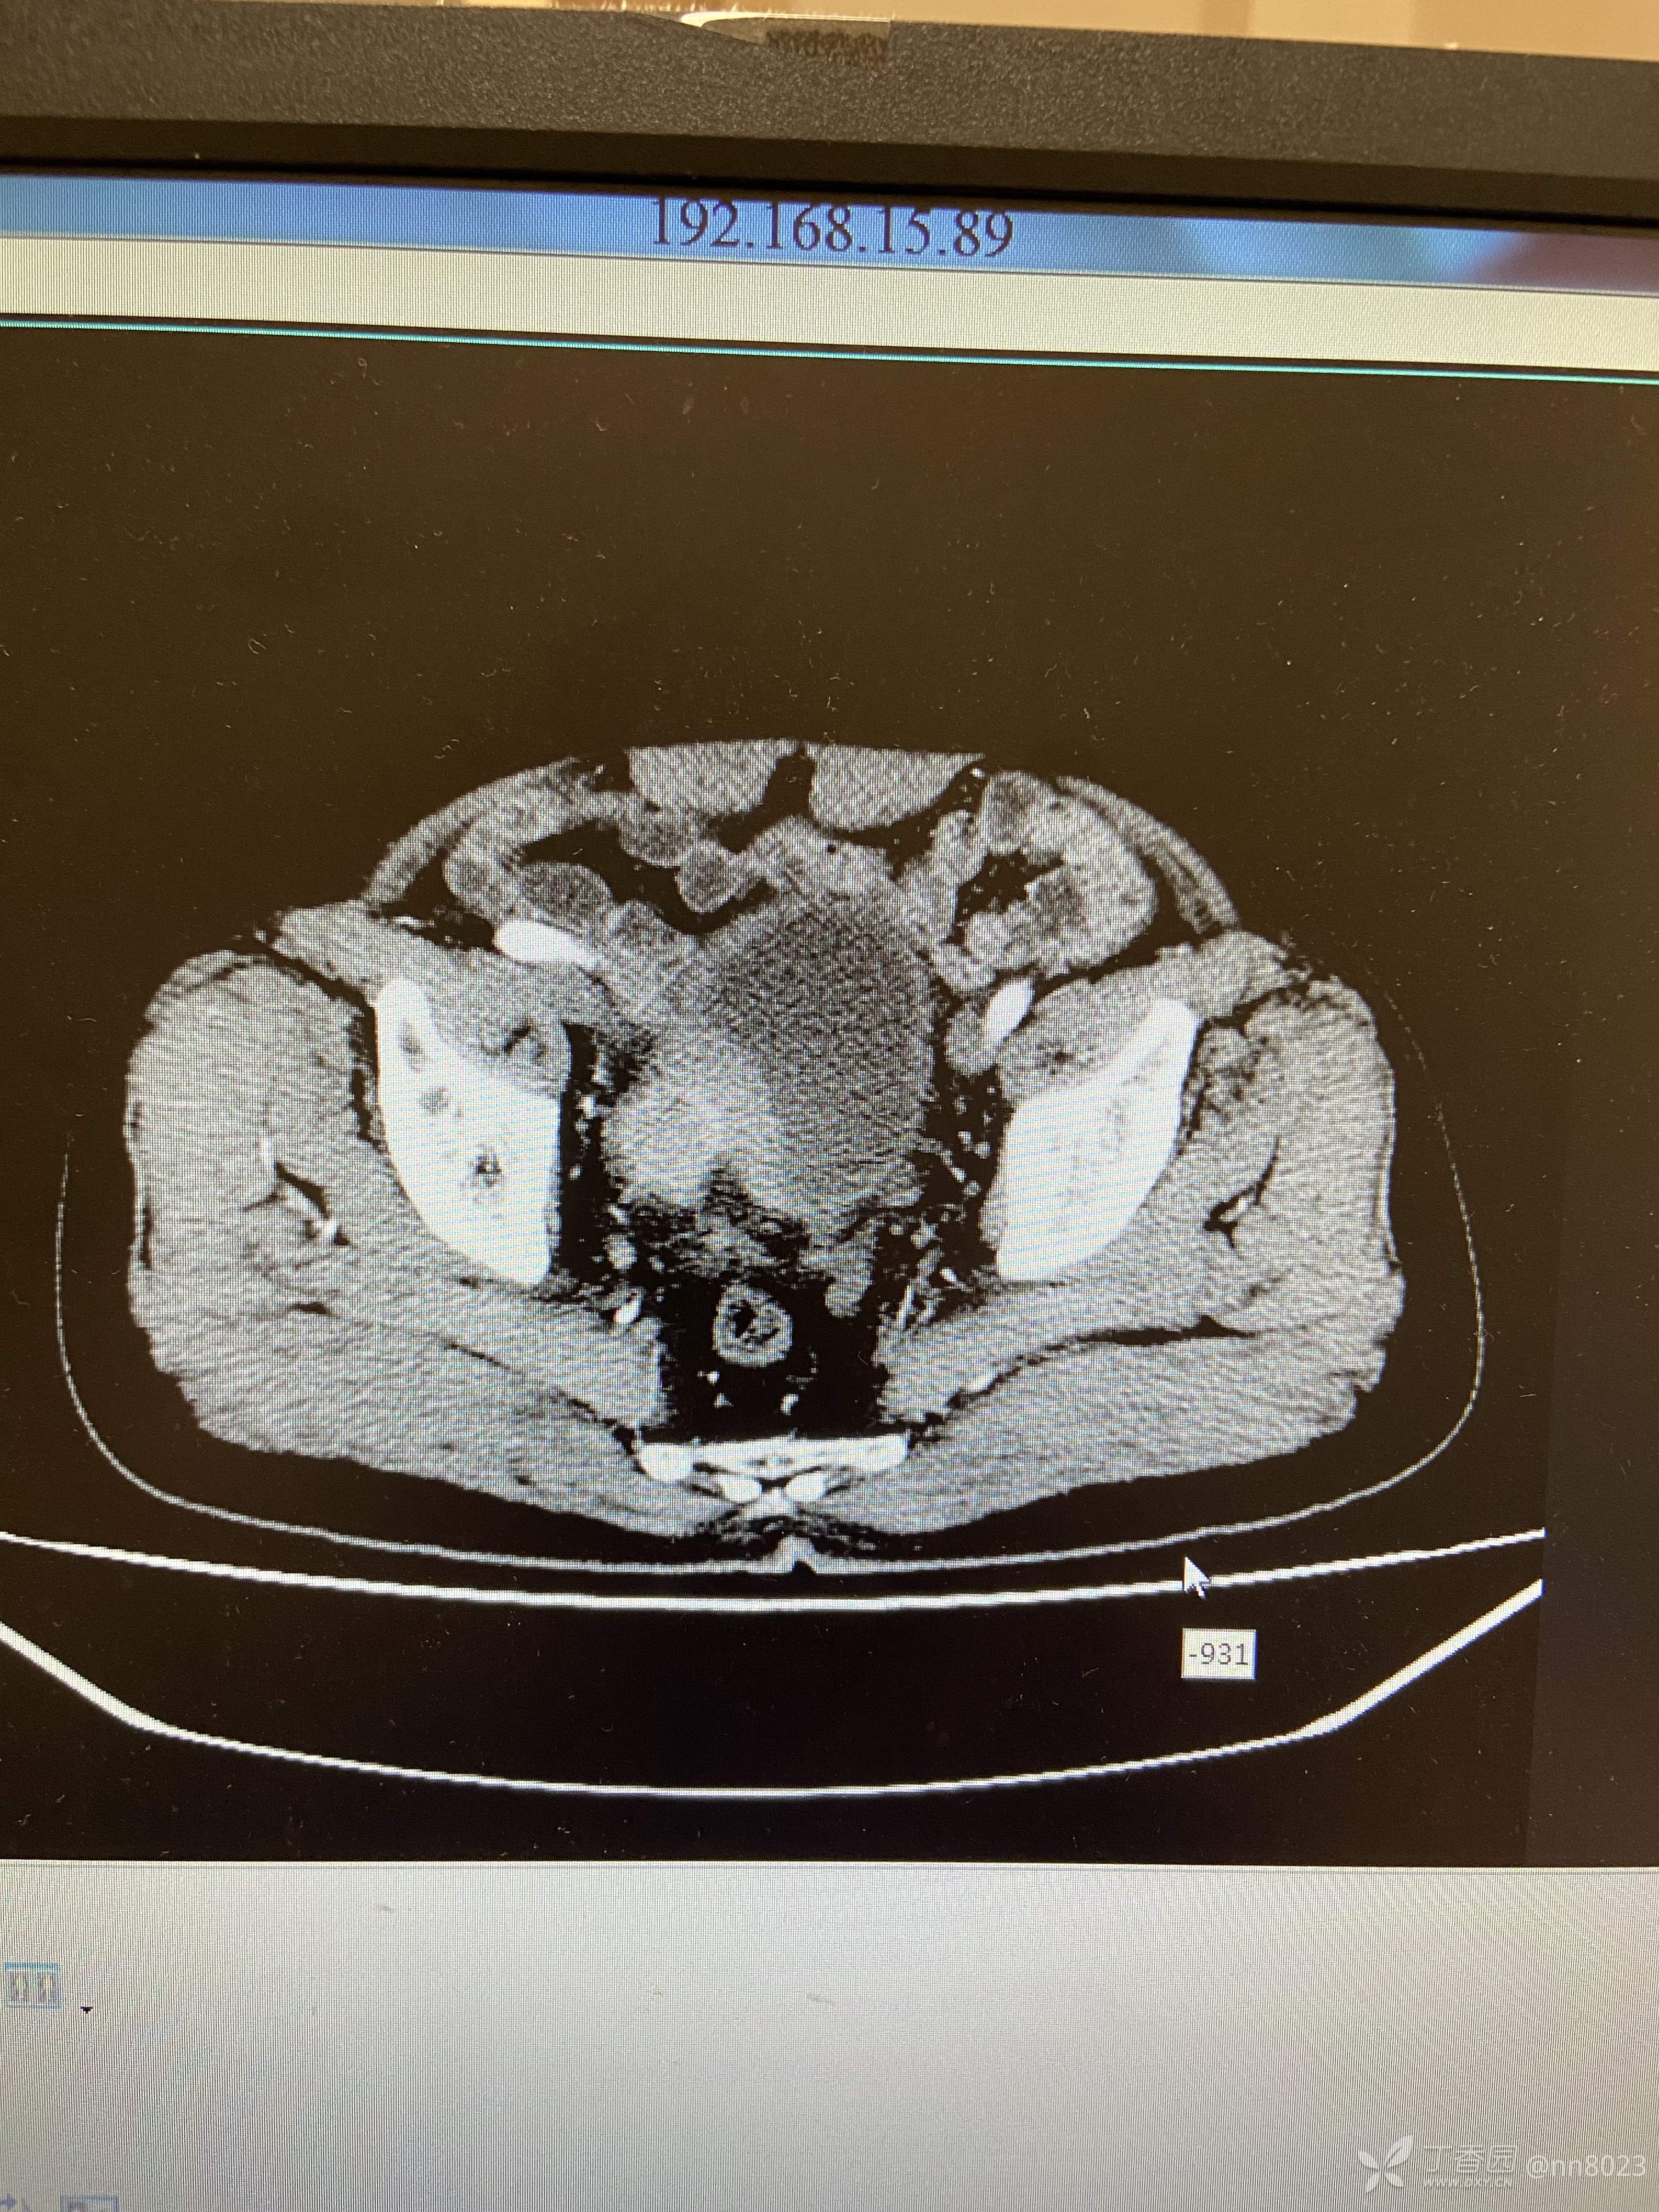

xiaospring +3 丁当66岁男性患者,因尿频尿痛于当地医院检查,彩超提示膀胱占位,完善增强CT